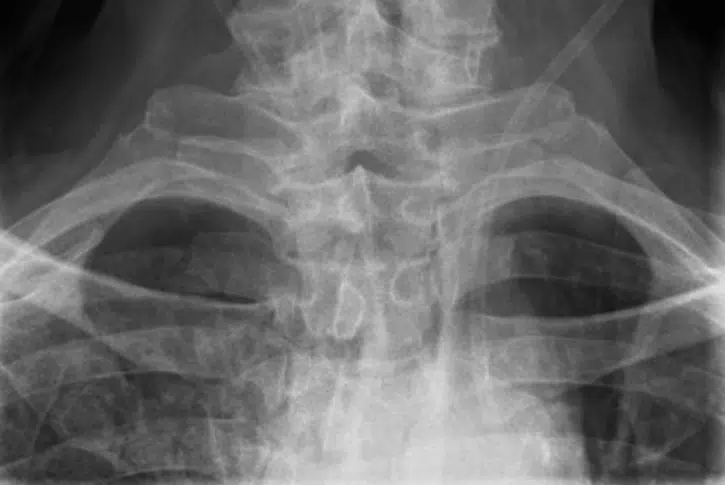

Un Britannique de 72 ans a mis sa santé en péril à cause d'un simple oubli. En effet, il devait se rendre à l'hôpital pour une opération de la paroi abdominale. Malheureusement, lorsqu'il s'est fait anesthésier, il a oublié de retirer sa prothèse dentaire. Sans s'en rendre compte, il l'a donc avalée durant l'opération. Six jours après l'opération, il s'est à nouveau présenté à l'hôpital, car il se plaignait d'avoir du sang dans la bouche, des difficultés à avaler et d'avoir extrêmement mal à la gorge dès qu'il mangeait un aliment solide. On vous parlait aussi de cet homme qui avait avalé un poisson vénéneux pour un pari et qui se l'était coincé dans la gorge. Les médecins ont d'abord pensé qu'il s'agissait d'une infection respiratoire et lui ont donc prescrit des médicaments. Deux jours plus tard, le patient est revenu, car ses symptômes avaient empiré. Il avait la voix rauque et du mal à respirer.

C'est là que les médecins ont découvert la présence d'un objet semi-circulaire durant un examen endoscopique de sa gorge. L'homme a alors fait le rapprochement avec sa prothèse dentaire qu'il pensait avoir perdu. Il a donc été opéré d'urgence pour retirer l'objet. Mais suite à cette opération, il a été blessé à l'intérieur du gosier, et a dû retourner se faire soigner et réopéré pour des saignements persistants dus à une artère déchirée par l'objet. Il a mis en tout, plus de six semaines pour retrouver la forme.